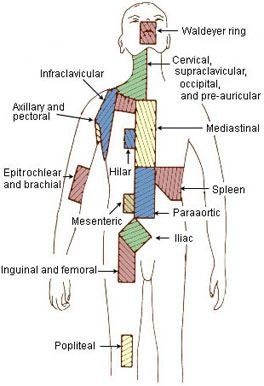

Zones Of Lymph Nodes

Hilar Lymph Nodes Map

Regional Lymph Nodes | SEER Training

lymph nodes regional lymphoma seer node regions anatomy diaphragm preauricular man above staging cancer hodgkin anatomical

Ann Arbor Staging System | Radiology Reference Article | Radiopaedia.org

radiopaedia lymph nodes anatomy arbor staging radiology cotswolds modified lymphatic spine armpit groin axillary

Ann arbor staging system. Lymph system lymphatic nodes abdomen presentation ppt node mesenteric superior intestinal powerpoint inferior trunk. Hilar lymph nodes map